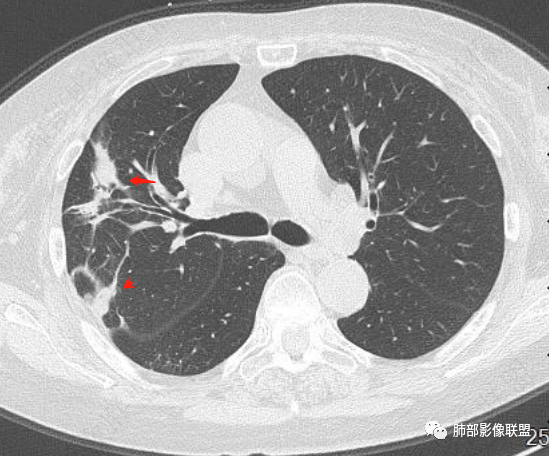

放射小白: 晨读病例:女性,70岁,风湿性多肌痛病史,右肺见不规则结节,边缘及周围见纤维索条影,考虑OP,药物性肺损伤。

谢加平: 右肺上叶外周,近胸膜下结节病灶,侧向融合,边缘清,见平直边,与胸膜平行分布,支气管进入略扩张,周围见多发长索条影,方向肉芽肿性炎症,建议隐球菌荚膜抗原检查,肿瘤不支持,经皮肺穿刺病理检查!

小兜: 晨读,女,70岁,风湿性多肌痛病史一年,半月前体检发现肺部阴影,无症状,口服药物治疗。现片示:右肺胸膜下条形实变影,局部层面似见多结节融合,周边伴条索影。下方近叶间胸膜处斑片状实变影伴条索影,宽基底与胸膜相连。综合考虑为炎性病变,隐球菌或OP可能

宇宙: 右肺上叶胸膜下结节,多结节融合,长轴平行胸膜,边缘模糊,周围长索条,胸膜牵拉,近端支气管充气扩张,考虑隐球菌,鉴别OP

衡妈: 老年女性,右肺上叶沿胸膜下不规则实性病灶,长轴平行于胸膜,有结节融合感,边缘部分彭隆部分平直,周围可见数条纤维灶影,病灶内可见充气支气管征未达远端,首诊考虑慢性炎性肉芽肿,隐球菌?机化性肺炎?建议增强扫描及ct下穿刺活检。

晨读:女,70,未诉症状。风湿性多肌痛病史,口服强的松等药物治疗。胸部CT:右肺上叶多发不规则斑片影,沿支气管分布,部分病灶侧向融合、平行于胸膜,边缘平直内收为主、部分彭隆,周围模糊晕、可见数条纤维灶影,胸膜牵拉,病灶内可见充气支气管征、管腔不畅,考虑慢性炎症,PC?OP?鉴别腺Ca、SCLC等。

南边: 这个病例大方向没问题,炎性。目前大家都是考虑:隐球菌病、OP,其实这两个结论有重叠,而且这个病例很值得讨论,可惜,估计没有证实。影像特点:病灶长轴与胸膜平行,侧向融合特点明显,符合隐球菌病,问题是目前的状态,边缘收缩明显

内部支气管扩张,周围少量GGO,而且病灶离开了胸膜,附近长索条影,支持机化的改变